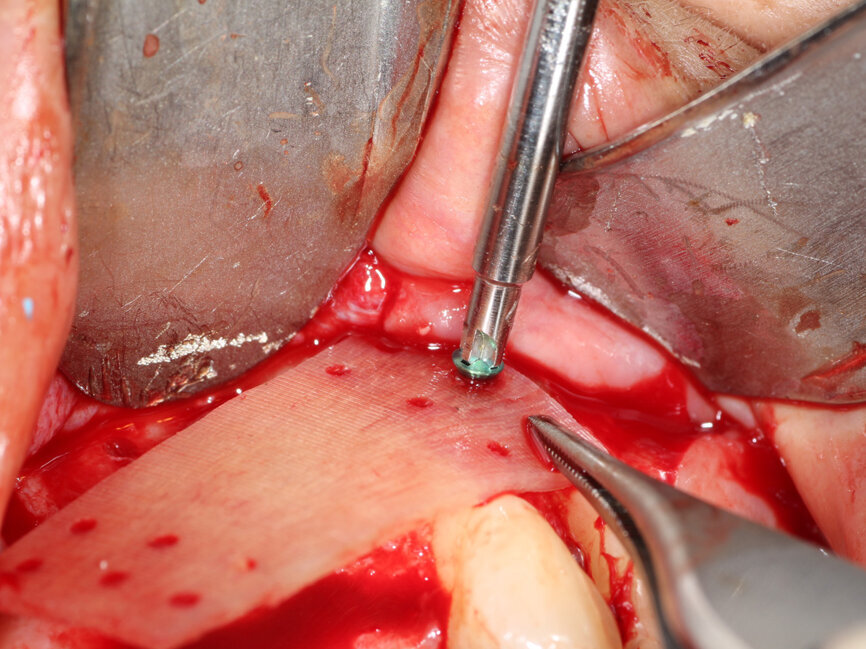

Fig. 4: The facial plate is fenestrated with a bur through the cortical bone in the edentulous space that will receive the osseous graft.

A #15 scalpel was utilized to create a vertical releasing incision between the right canine and lateral incisors and also between the left first and second premolars. These were connected by a facial sulcular incision medial to the vertical releasing incisions and a midcrestal incision at the edentulous area. A full thickness flap was elevated extending past the mucogingival junction to exposure the deficient area as well as bone covering the roots of the adjacent teeth (Fig. 3). A thin ridge with a notable concavity at the edentulous area was confirmed correlating with what was accessed on the CBCT exam. A three sided 1.2 mm bur from MedEquip Dental Supplies in a surgical handpiece was utilized to create multiple decortication points through the cortical bone to the underlying cancellous bone (Fig. 4). This is performed to allow endosteal osteoblasts from the cancellous bone to interact with the graft, grow bone around and within the particulate graft particle, and to accelerate vascularization of the graft and incorporation to the osseous bed.